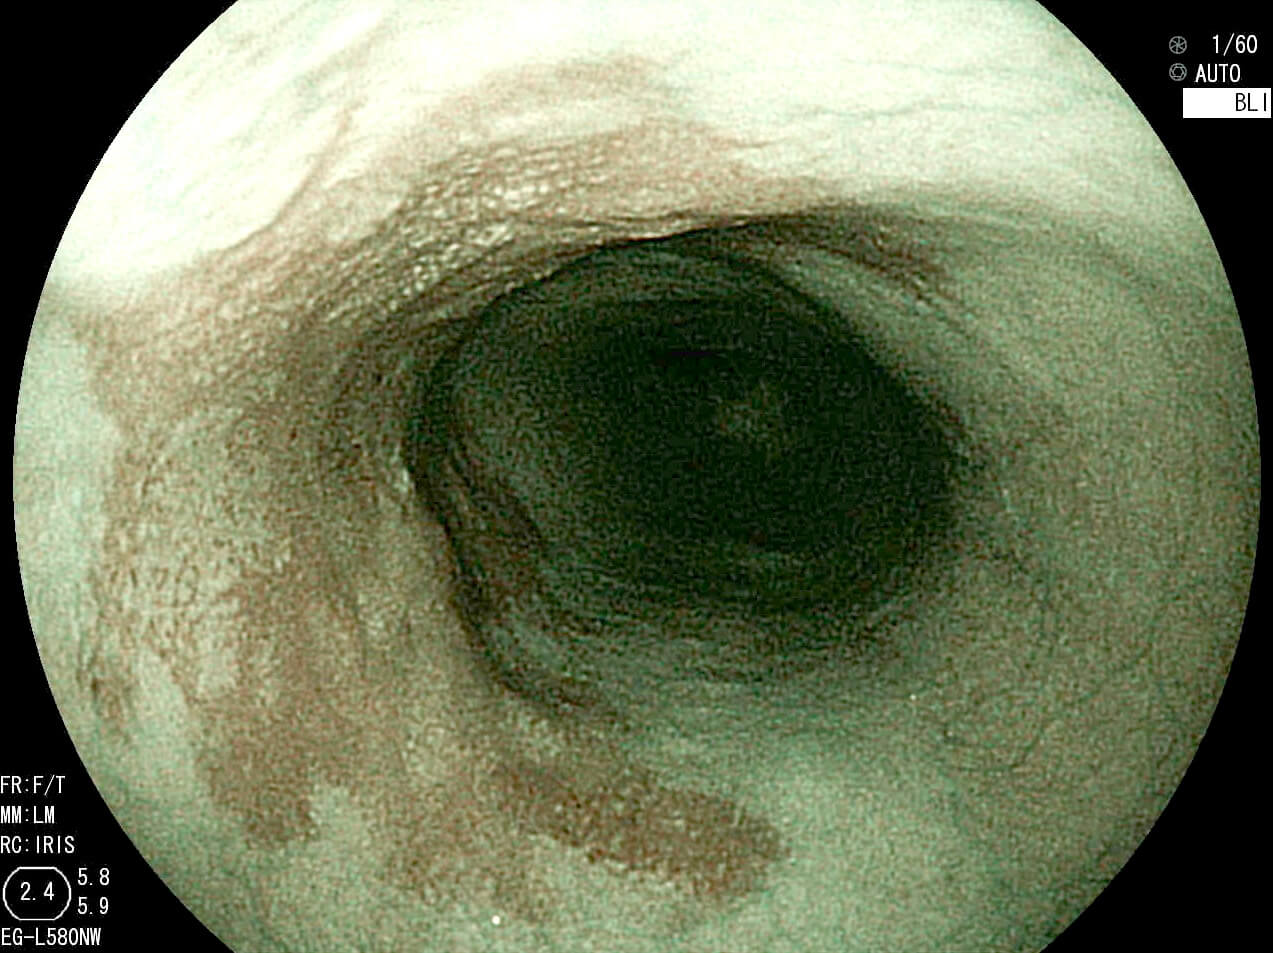

- Blue LASER Imaging (BLI)

- Blue LASER Imaging とは表面血管観察に適した短波長レーザー光を照射して得られる画像と白色光画像と画像処理することによって血管や表面構造の観察に適した画像を表示するものです。

と、難しい説明は置いておいて、実際の写真をみてみましょう。

上の写真は早期食道がんです。通常光の観察(左写真)(上写真)では癌の領域が不明瞭ですが、レーザー光源(右写真)(下写真)ですと、食道がんの領域が茶褐色となり、境界が一目瞭然です。このようにがんを早期で発見することにより、内視鏡で治療することが可能になります。